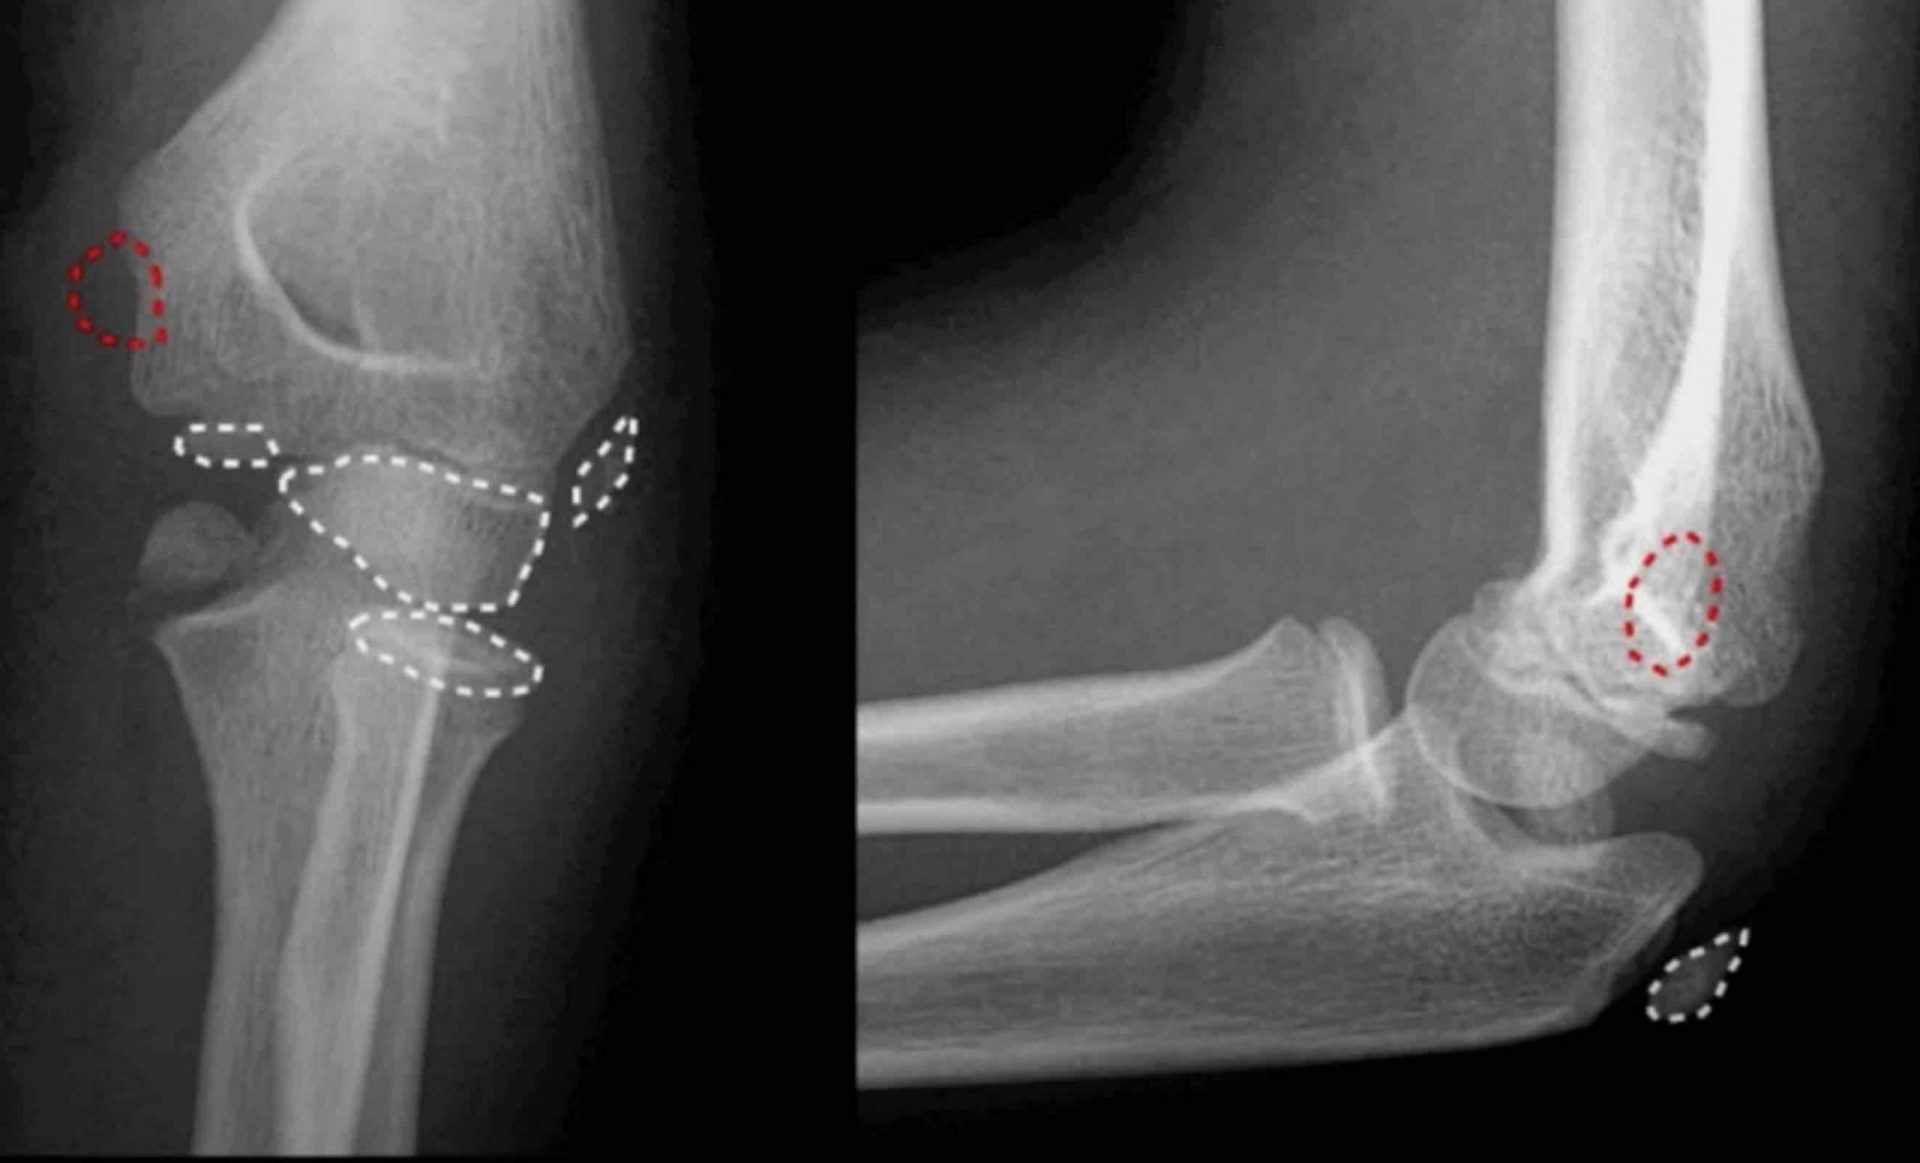

שבר במרפק עלול להתרחש במספר אזורים מרכזיים:

- אולקרנון, הקצה האחורי הבולט של המרפק

- ראש הרדיוס בעצם האמה

- עצם הזרוע מעל המפרק

שבר באולקרנון ופגיעות טראומה ישירה

האולקרנון הוא אחד האזורים הפגיעים ביותר במרפק. מיקומו החיצוני והיעדר הגנה שרירית הופכים אותו לרגיש במיוחד לפגיעות ישירות בנפילות ובתאונות.

כאשר השבר מלווה בתזוזה, מבצעים לרוב קיבוע פנימי בניתוח באמצעות פלטות, ברגים או סיכות קירשנר. קיבוע בגבס בלבד אינו מספק ברוב המקרים, משום ששריר הזרוע האחורי מפעיל כוח מתמיד המושך את השבר ממקומו.